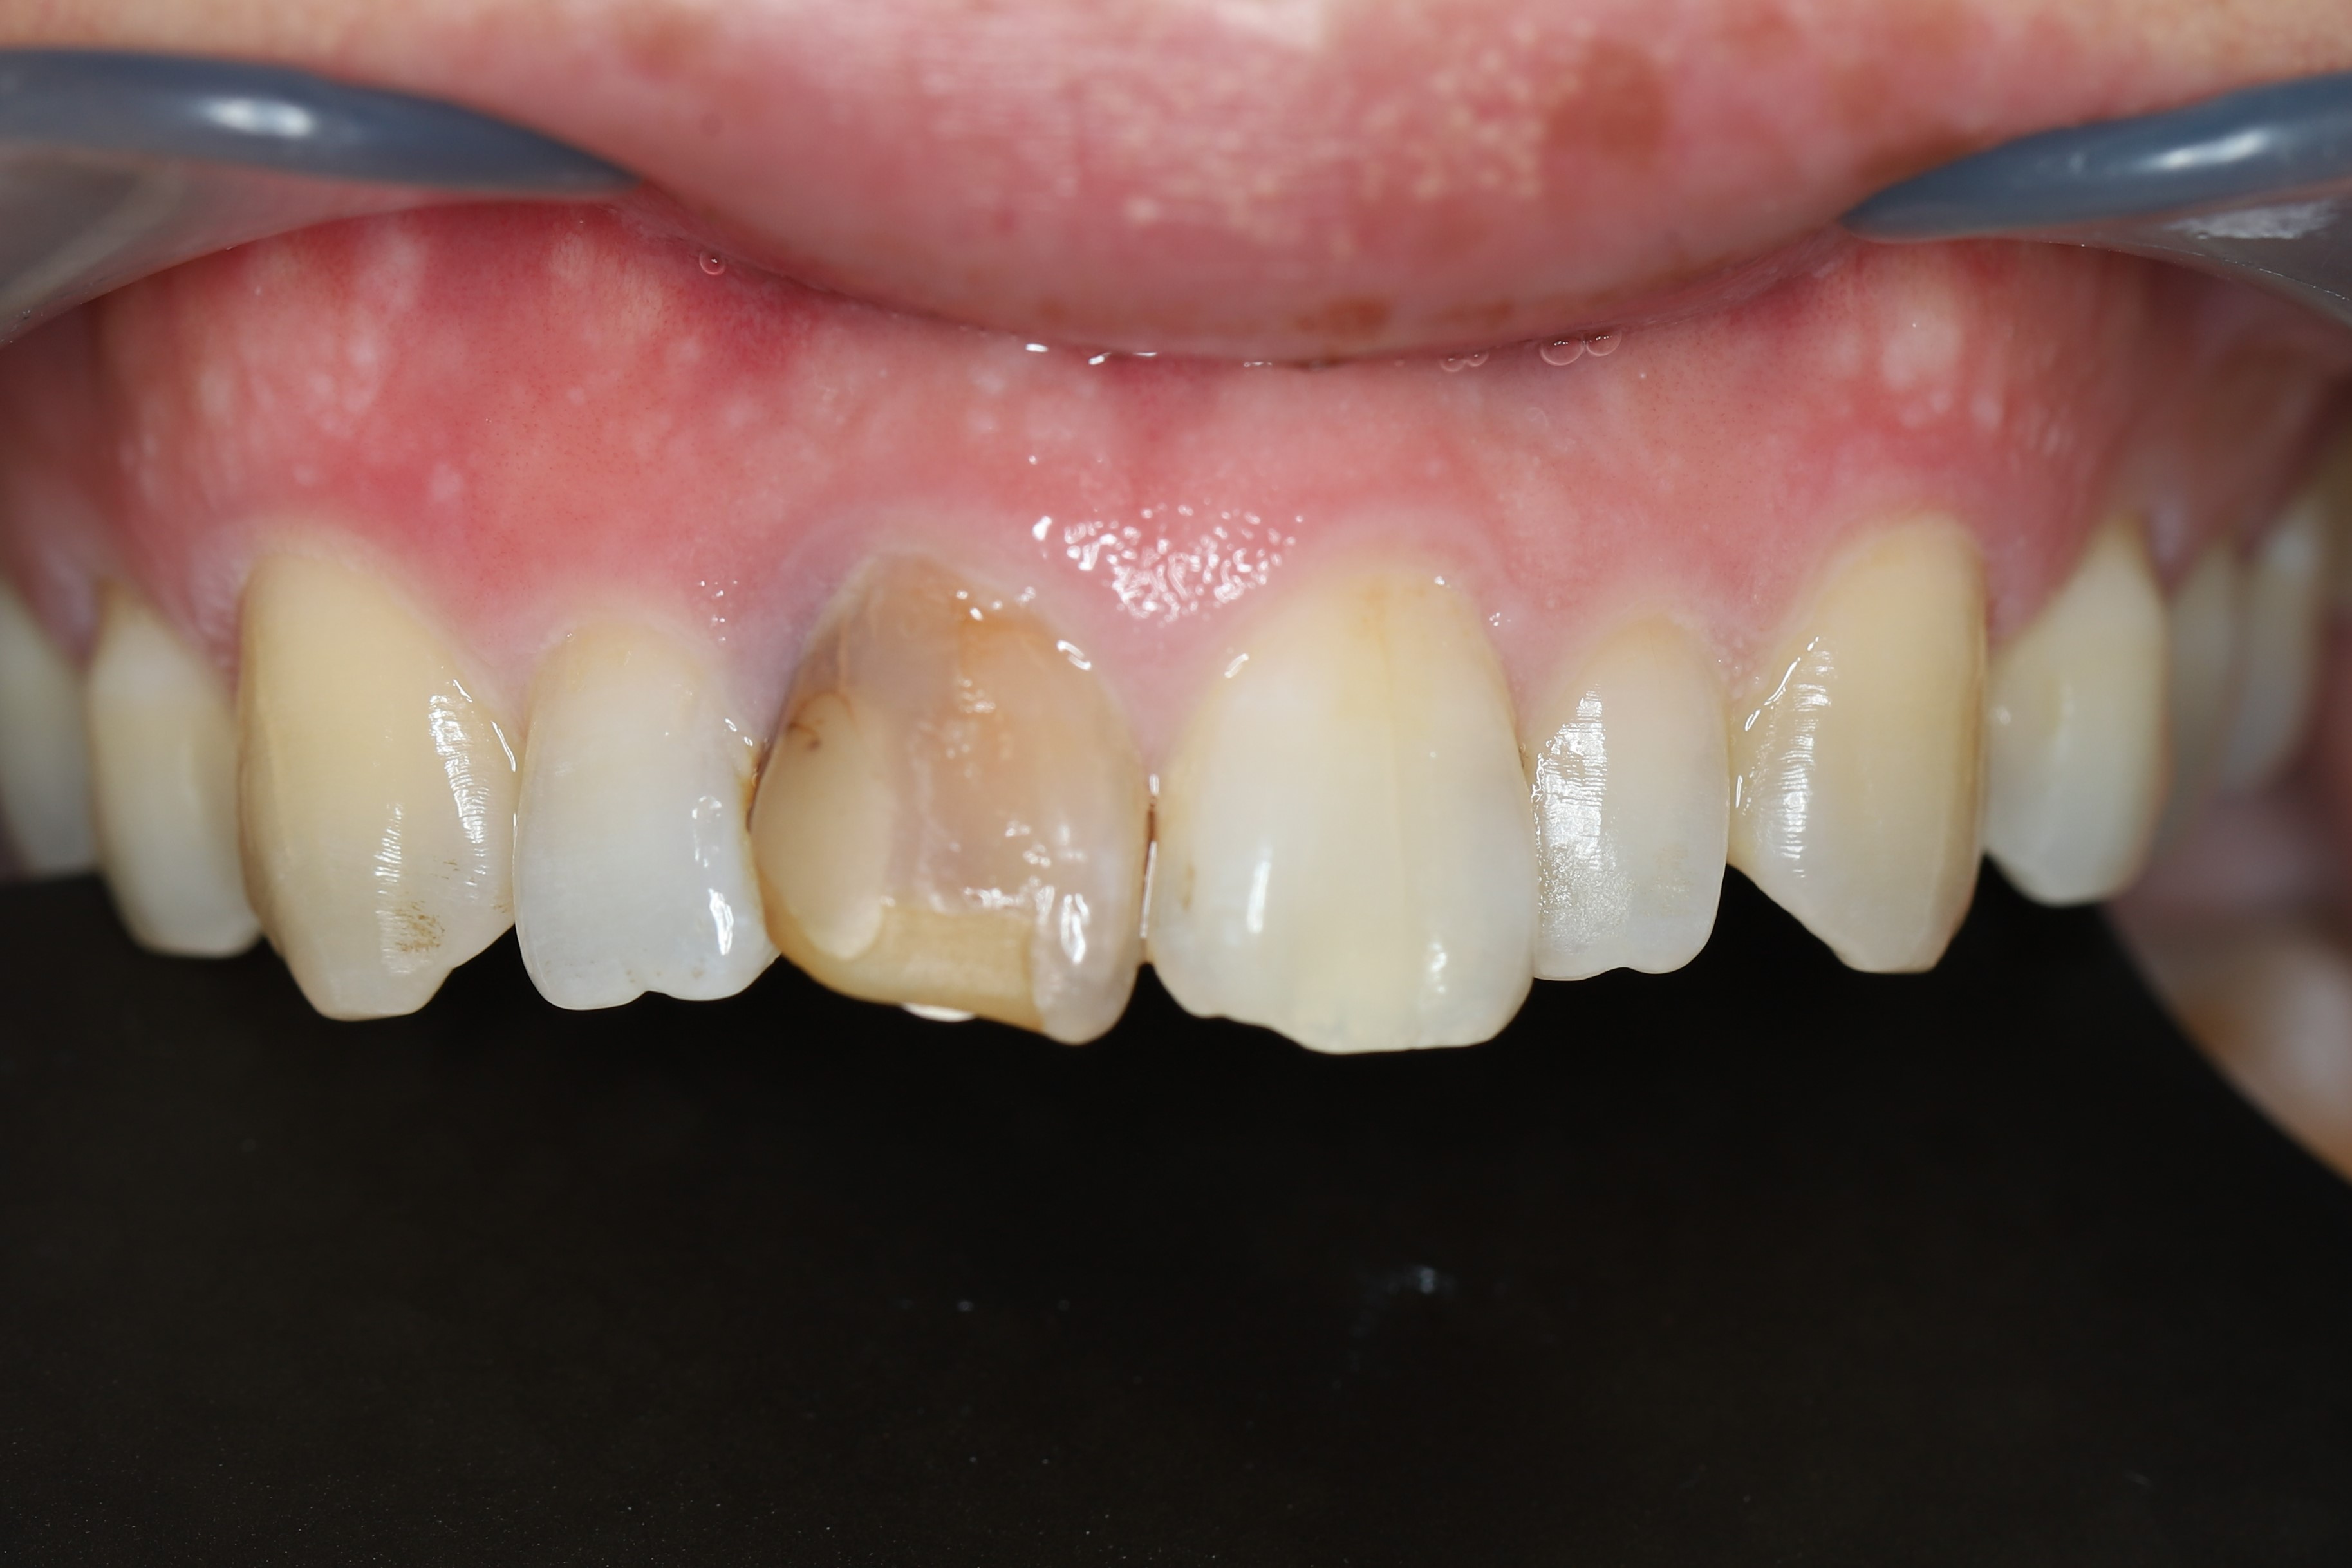

症例2(歯の色+形に問題がある場合)

治療前

ホワイトニング後(治療期間2ヶ月)

虫歯を除去し、最小限の切削量で被せ物により歯の形を改善後